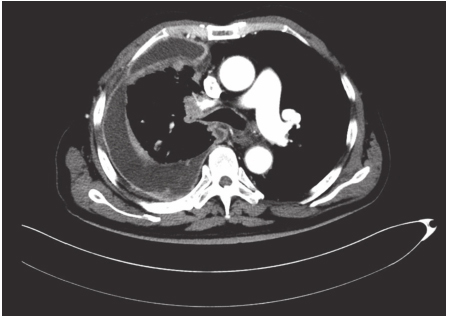

通过CT检查少量的胸腔积液亦能显影。CT的优点还包括通过病灶密度观察可将局限包裹性积液与肺实质病变加以鉴别;强化造影后可较好地显示纵隔、肺门、气管旁淋巴结、肺内肿块及胸膜病变等(图2-13-3)。

图2-13-3 渗出性胸膜炎强化CT